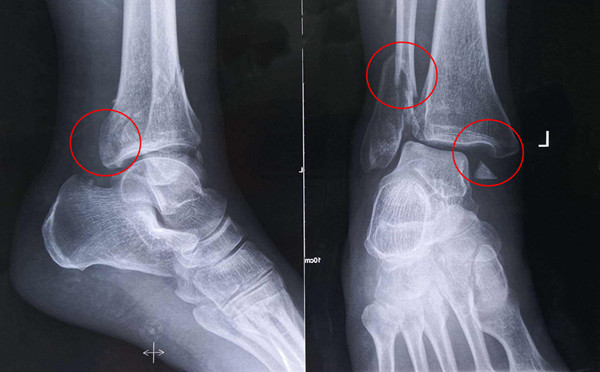

【醫(yī)療科普】之三踝骨折

三踝骨折